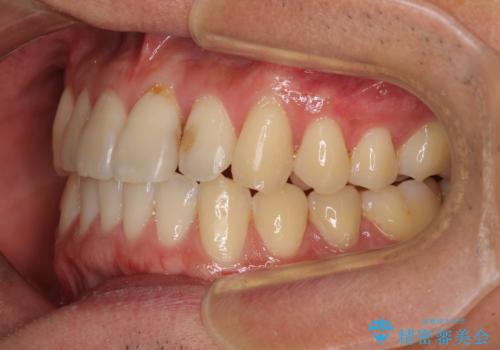

気になる前歯のデコボコをインビザラインで解消

- 前歯のデコボコを気にして来院された患者様です。

主に下顎歯列全体の後方移動とIPR(歯と歯の間を削る)によってデコボコが解消するように設計し、インビザラインにより治療を行うこととしました。

インビザライン矯正特有の、治療後半で前歯のみが強く接触する症状が発現し、咬み合わせ改善に期間を要することとなりました。